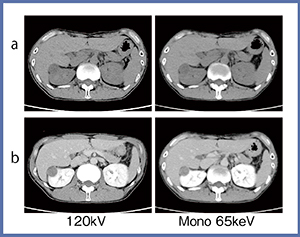

また,臨床では従来の120kVで撮影した画像に近いイメージが要求されることから,仮想単色X線画像でCT値を計測し120kVと近い値になるkeVを検証した(図4)。ファントムに軟部組織を模した濃度の異なる砂糖水を挿入して,仮想単色X線画像のkeVごとのCT値を計測し,120kVと近いCT値となるkeVを求めたところ,約65keVが最も近いことが示された。腹部の臨床画像で,65keVの仮想単色X線画像と120kV画像を比較したところ,単純画像(図5a)では違和感のないコントラストの画像が得られている。造影効果としては,仮想単色X線画像では腎臓を中心に造影効果の上昇が見られた(図5b)。

図5 120kV画像と仮想単色X線画像(65keV)との比較